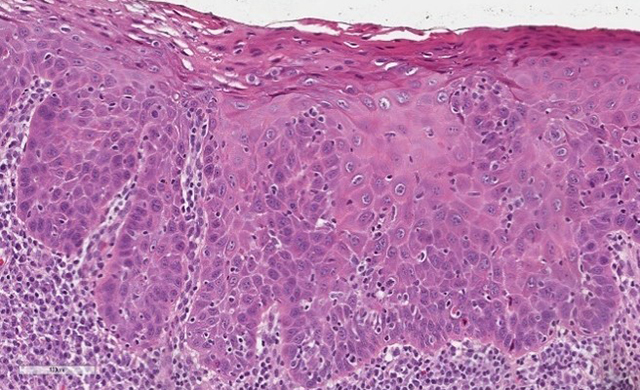

InVivage® is an intra-oral digital endomicroscope that offers the power of single-cell oral imaging at your fingertips. InVivage® by Optiscan is built with our unique patented 3D imaging technology, providing live microscopic oral imaging solutions in optimal resolution, and unlimited image capture to assist in immediate informed decision making.

- Incorporates the latest Optiscan technology for slide-free, biopsy-free, non-destructive cellular imaging

- Optimized for imaging cellular architecture, in clinical and research settings, at single cell level

- Images easily interpreted using recognized WHO diagnostic criteria for oral epithelial dysplasia

InVivage® can help clinicians distinguish normal, precancerous and cancerous oral tissue.